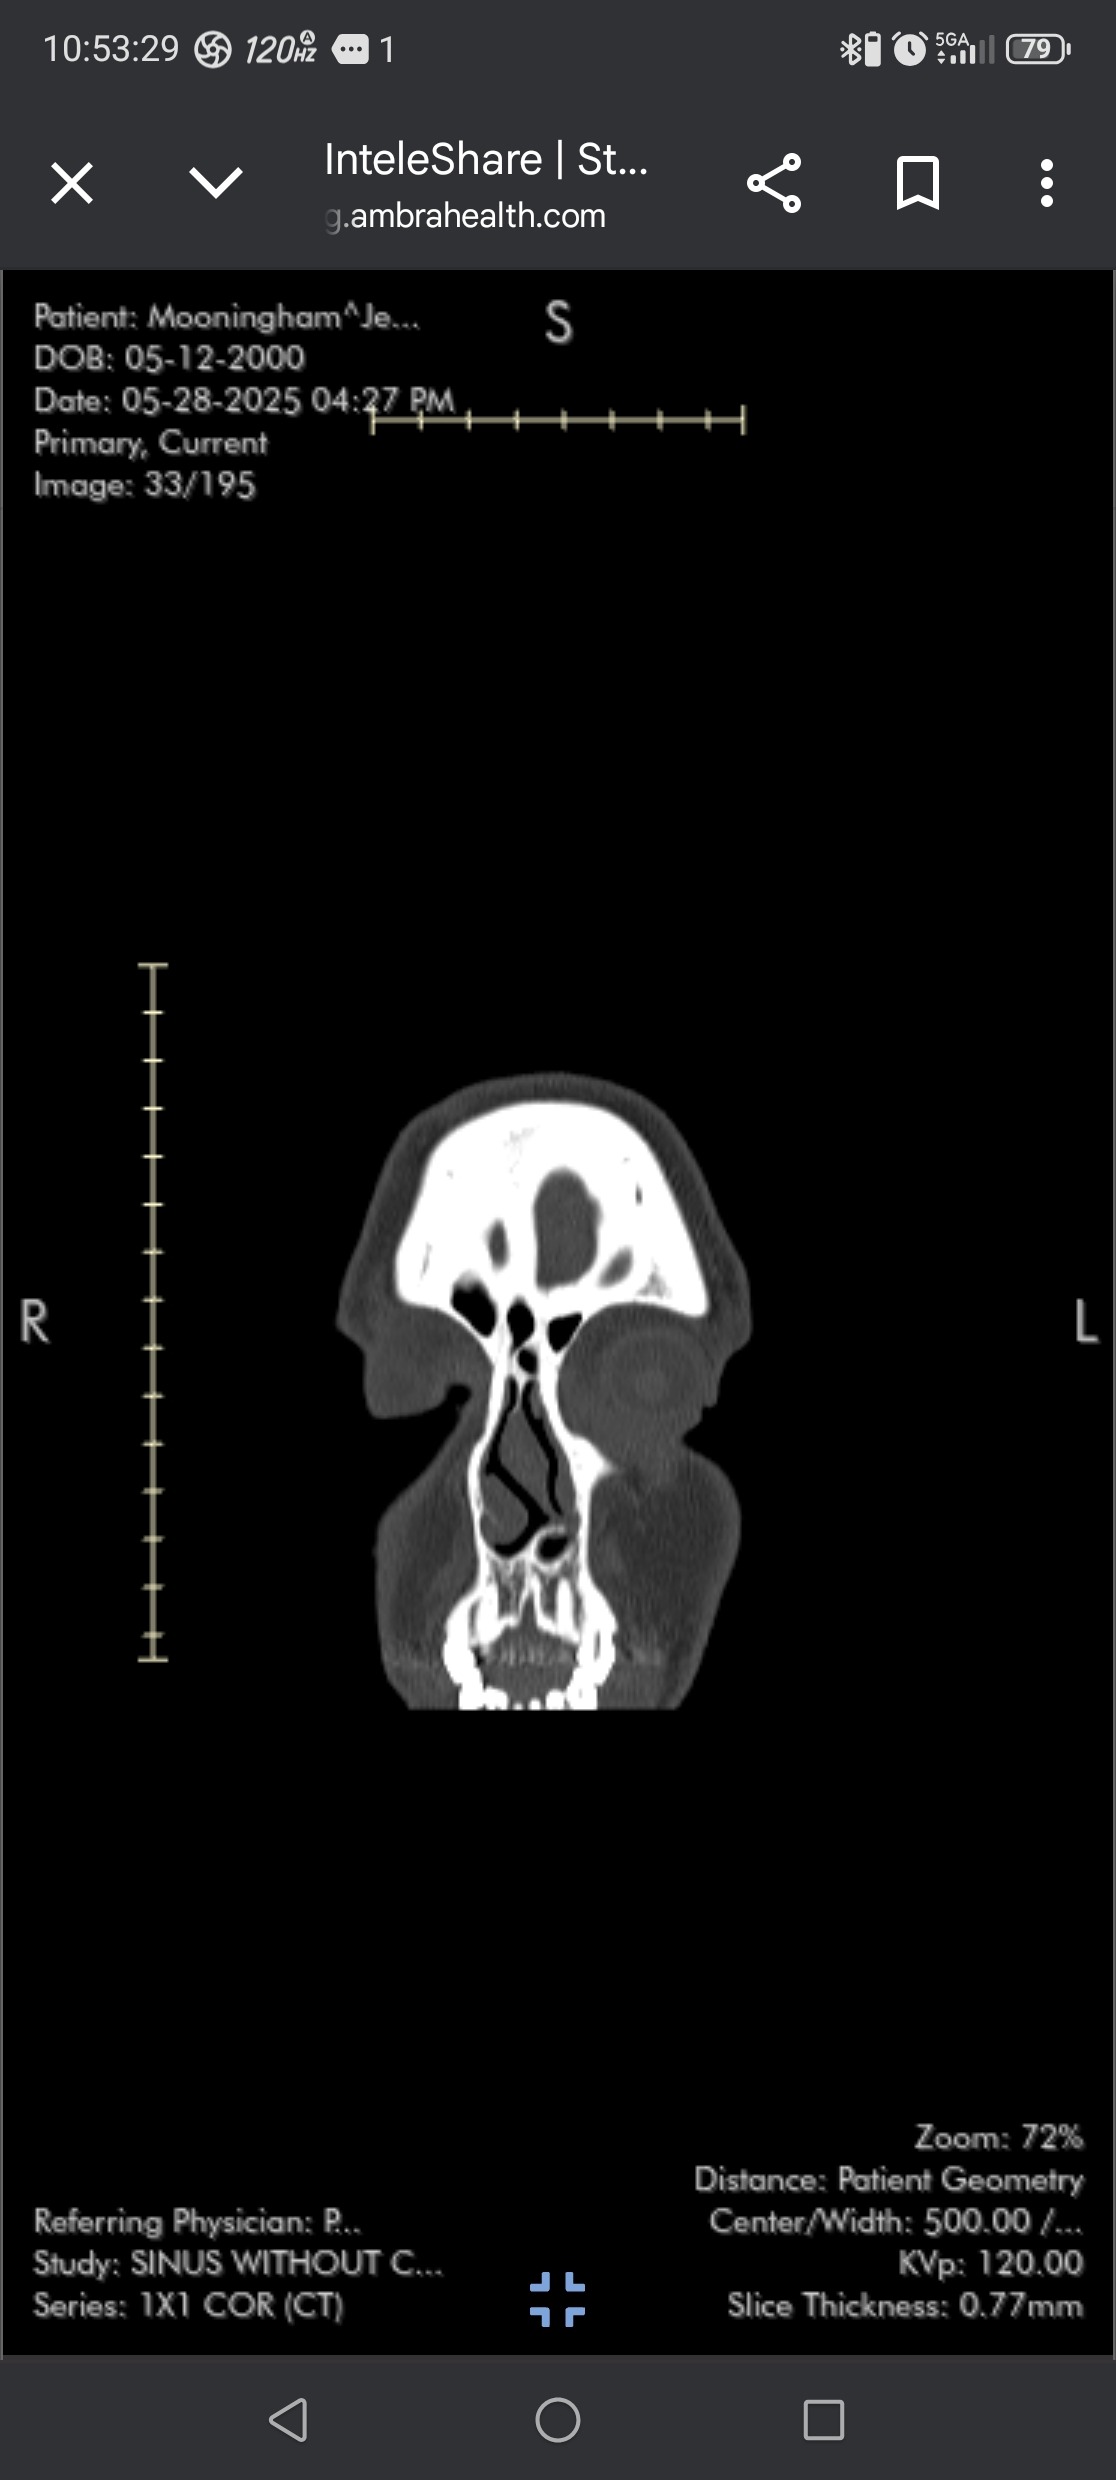

Hi, I’m Jenna. I’m preparing for major nasal and sinus surgery to fix something I’ve been quietly dealing with my entire life. I was born prematurely, weighing just 2 pounds and a few ounces, and my sinuses didn’t fully develop as they should have. Then between the ages of 4 and 6, I broke my nose three times — injuries that were never corrected.

Now at 25, I’m facing the long-term effects: a broken nose, a completely deviated septum, and collapsed sinuses that make it hard to breathe, sleep, or live comfortably day to day.

Repairing my collapsed sinuses